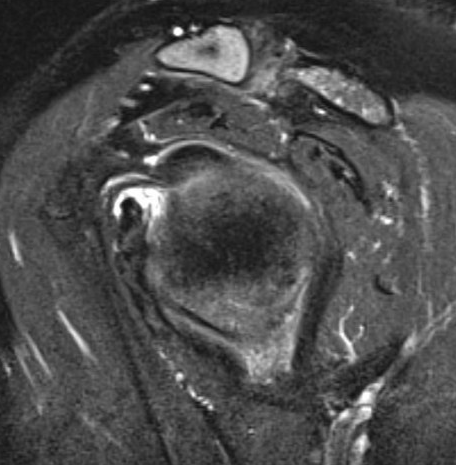

MRI

Thickened capsule and synovitis of axillary capsular recess